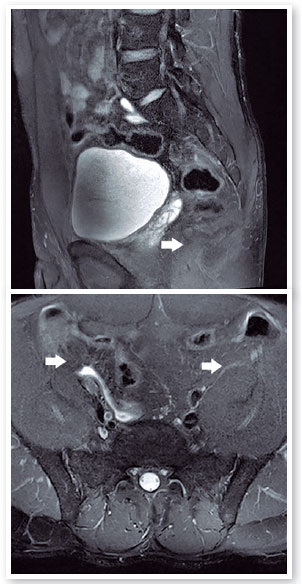

In the rheumatological evaluation, the patient presented low back pain with an inflammatory rhythm, and physical examinations showed a bilateral positive Fabere test, arthritis in the knees, and calcaneal enthesitis. Magnetic resonance imaging (MRI) of the sacroiliac joints showed bilateral sacroiliitis (Figure 1). With Bath Ankylosing Spondylitis Disease Activity Index (BASDAI) score of 4.5, a diagnostic hypothesis of nonradiographic axial spondyloarthritis was made. Sulfasalazine 2 g/day and a nonsteroidal anti-inflammatory drug (NSAID) were initially prescribed. The patient took this medication for 3 months without any clinical response. Prophylaxis for latent tuberculosis with isoniazid (300 mg/day) was initiated and maintained for 6 months. One month later, 5 mg/kg of infliximab, an immunobiological agent, was initiated (attack doses at 0, 2, and 6 weeks followed by every 8 weeks).

The ophthalmological examination presented a partial CVA of 20/20 in OU; IOP was 12 mmHg in OU; biomicroscopy of the OD showed no changes, whereas that of OS showed no keratic precipitates, but there were cells in the anterior chamber (1+/4+). RM showed no changes in OU. Topical prednisolone acetate (1%) in a regressive regimen and tropicamide (1%) were prescribed. Infectious causes were ruled out in the investigation. MRI of the sacroiliac joints showed slight subchondral bone edema on the iliac face of the left sacroiliac joint (Figure 2). The patient was positive for HLA-B27 and a 9-mm tuberculin PPD test.